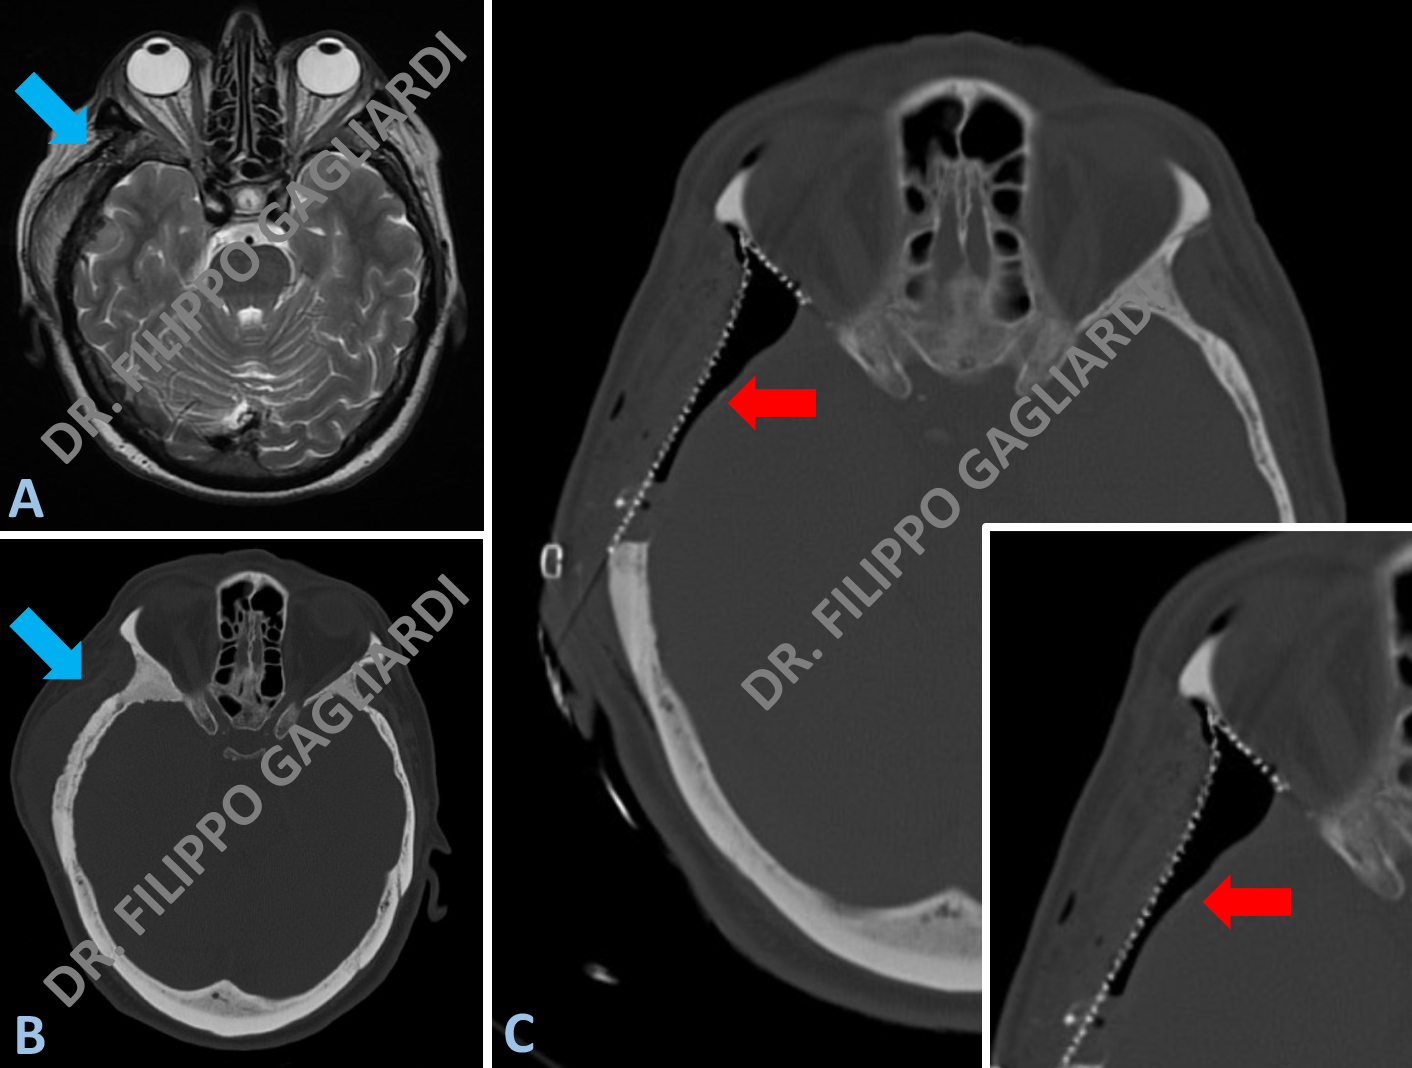

meningiomaCaso di voluminoso meningioma del terzo anteriore della falce. Si tratta di un tumore benigno che origina dell’involucro che ricopre il cervello (detto meninge). Le Figure A, B, C mostrano la lesione visualizzata alla RM pre-operatoria, rispettivamente nelle sequenze assiale e sagittale (laterale) dopo infusione di mezzo di contrasto e nella sequenza T2 coronale (antero-posteriore). Il tumore comprime il tessuto cerebrale sano, condizionando la dislocazione del cervello. Il Paziente è stato sottoposto ad un intervento di craniotomia ed asportazione radicale della lesione. La Figura D mostra la TC encefalo post-operatoria, che documenta i normali esiti di intervento. Le Figure E e F mostrano, invece, il controllo post-operatorio di RM encefalo rispettivamente nella sezione assiale e sagittale con il mezzo di contrasto. Si noti che la lesione risulta asportata radicalmente con conseguente riespansione del cervello, prima compresso.